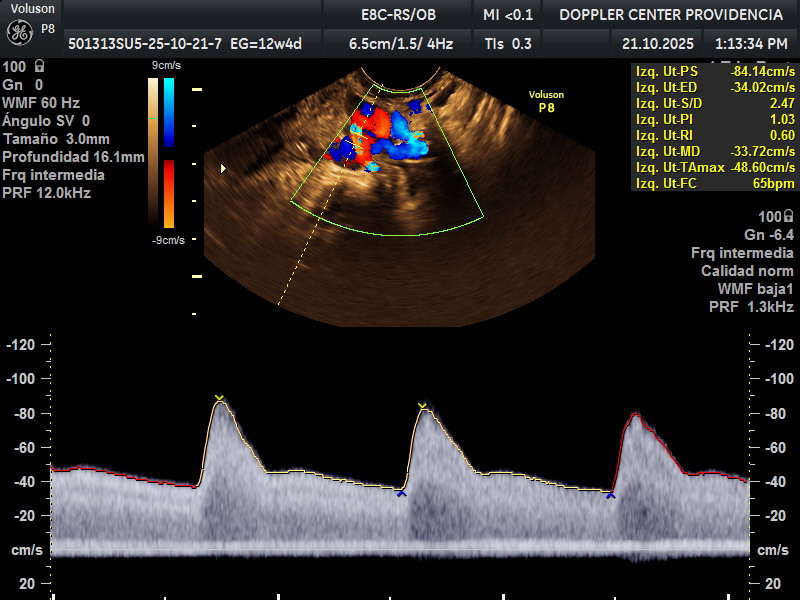

• Eco Doppler 11-14 semanas